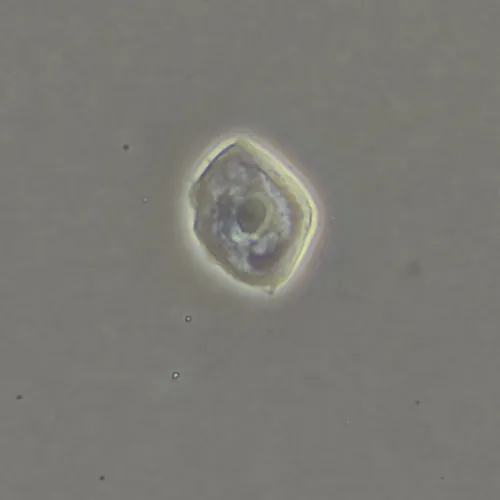

Фазово-контрастная микроскопия позволяет увидеть детали прозрачных образцов, которые практически не видны в светлом поле, и при этом не повреждать их окрашиванием. Метод применяют в разных сферах: медицине, биологии, ветеринарии, сельском хозяйстве, фармацевтике, экологии.

Оптика фазового объектива конструктивно дополнена фазовым кольцом в плоскости выходного зрачка. Фазовый объектив может работать и в фазовом контрасте, и в светлом поле, но в светлом поле демонстрирует не столь высокие результаты.